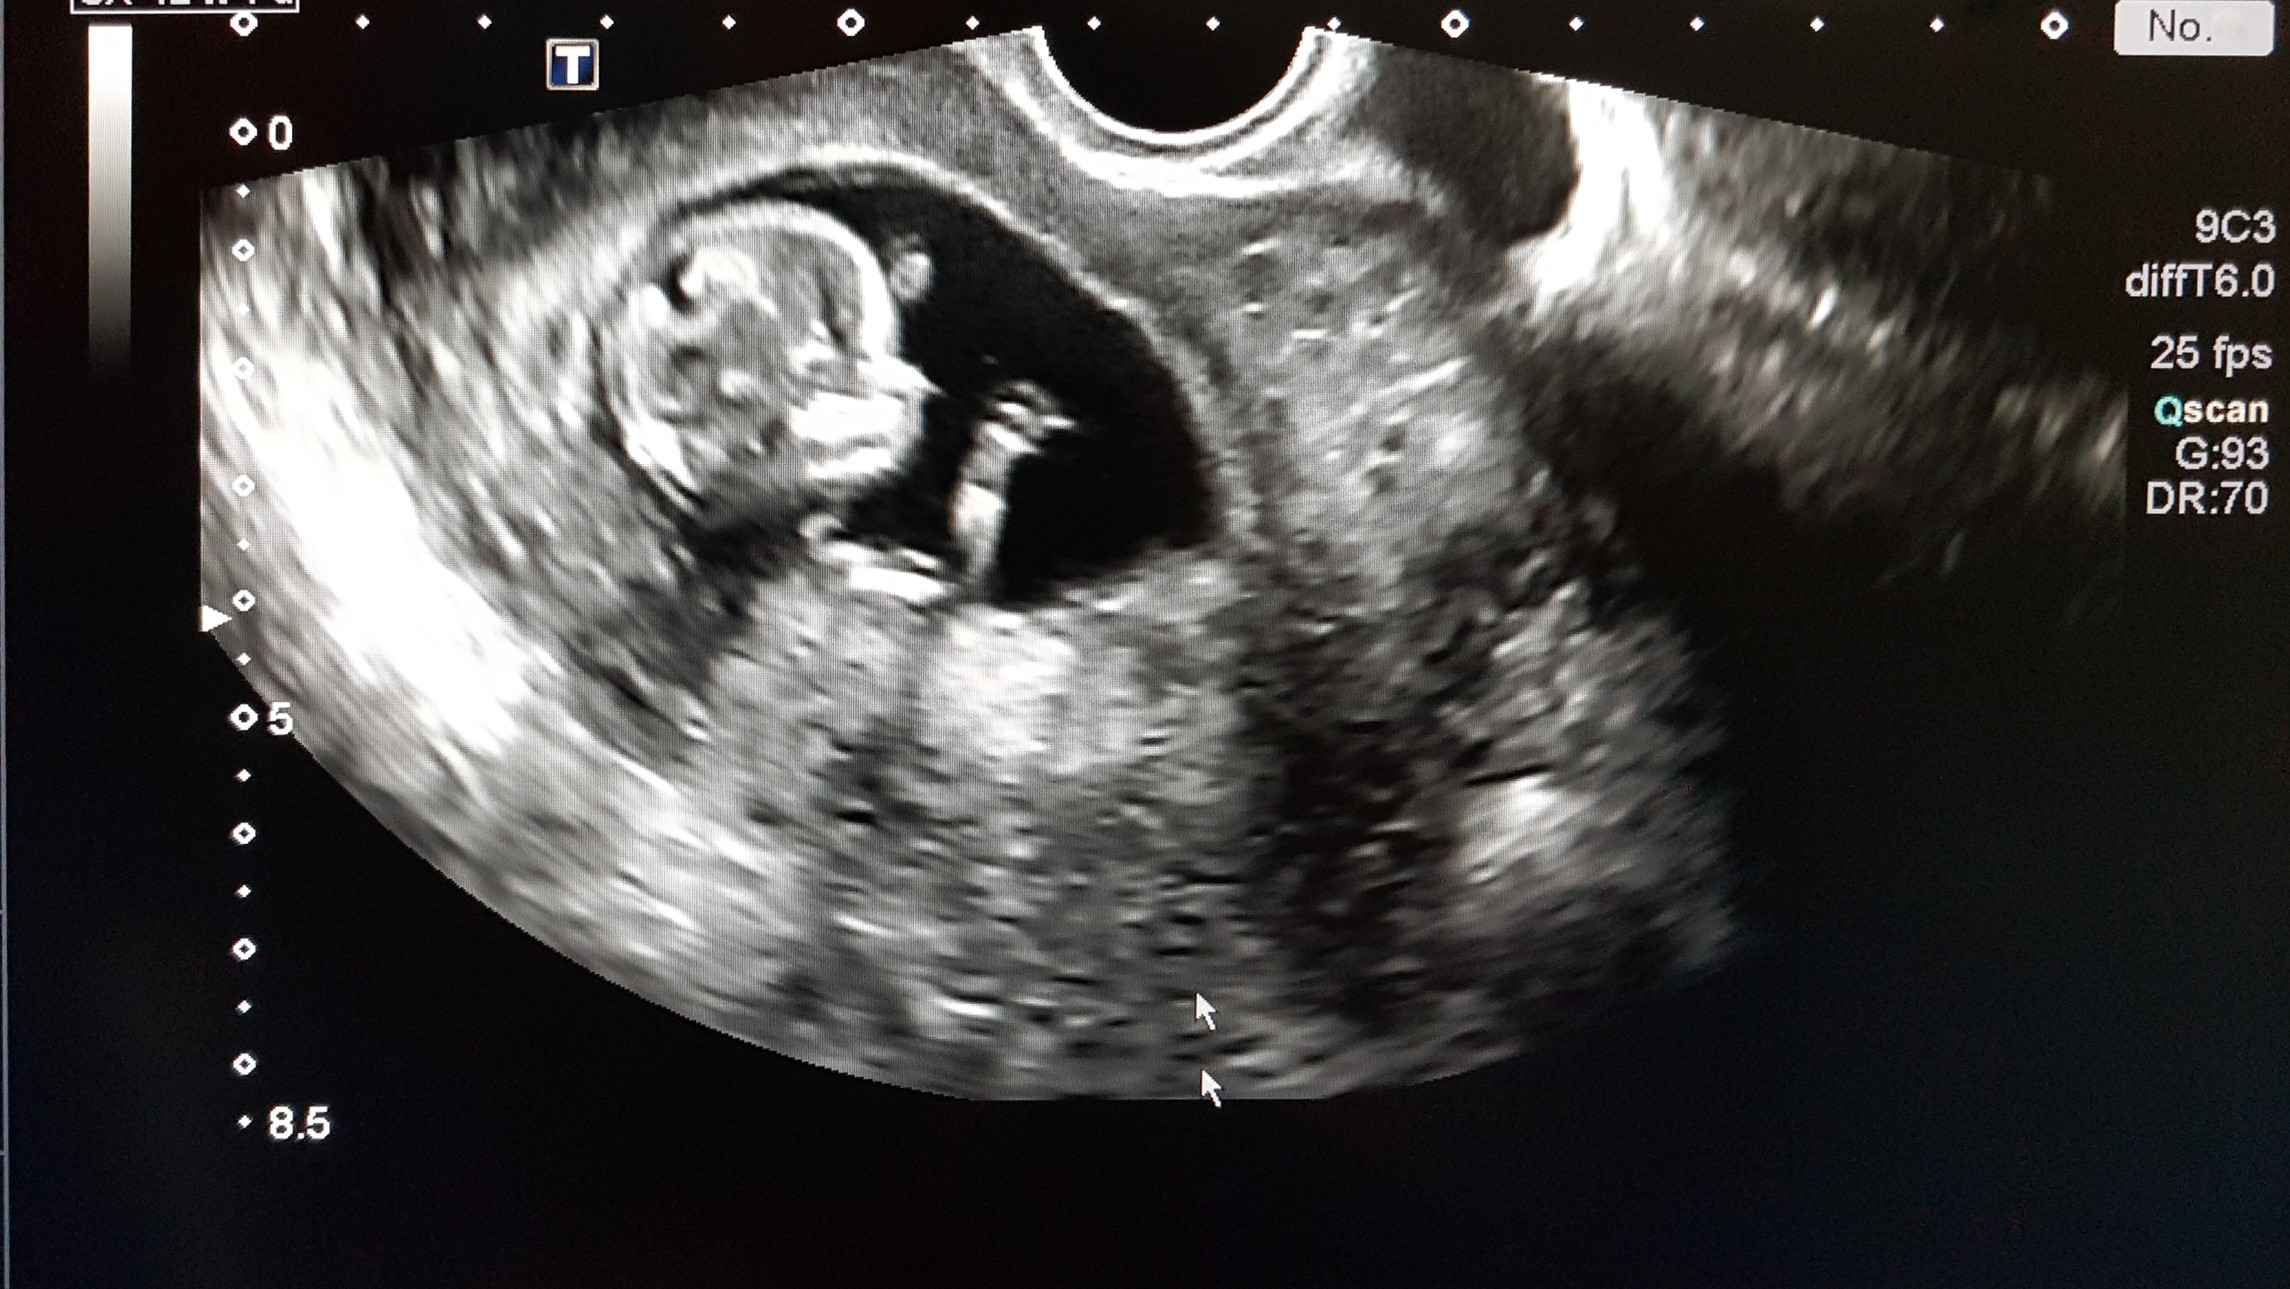

This is a developing human being who has his or her own unique DNA and one who most likely developed a detectable heartbeat at six weeks of development. At eight weeks, the unborn human’s lungs develop, and two weeks later, the brain and other vital organs are beginning to function, as the Virginia Department of Public Health notes. Even at 12 weeks, which is still in the first trimester, the unborn human can swallow. At 16 weeks, the unborn human is usually about 4 1/2 inches long and has its own movements inside of the womb (limbs and eyes), according to the Mayo Clinic.